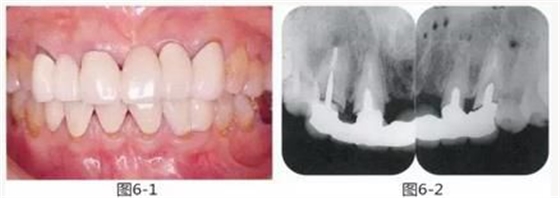

圖6-4,5

左上2,3和右上1,3存在齦下齲壞,但牙齒周圍有充足的角化齦。左上4和右上4頰側(cè)的角化齦較少。

圖6-6~8

左上3到右上3的牙齒,通過(guò)包含牙槽骨外科處理在內(nèi)的APF進(jìn)行治療,確保了獲得biologic width所必需的、3mm以上的健全牙體組織。為獲得附著齦,使用FGG對(duì)左上4和右上4的牙齒進(jìn)行了治療。

圖6-9 牙周外科治療5個(gè)月后,最終取模前的狀態(tài)?;乐車@得了充足的附著齦。